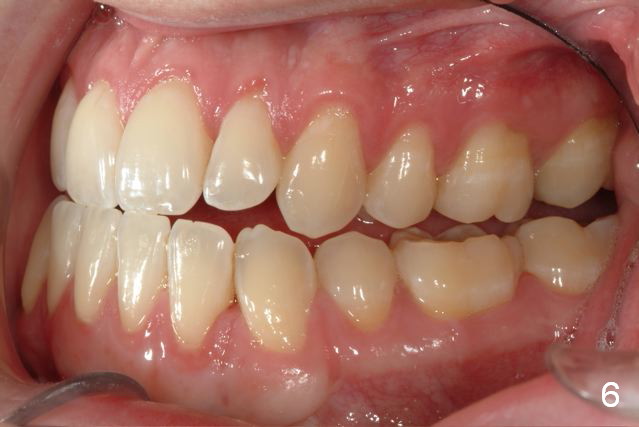

Maxillary Retrusion Post-Orthodontic Treatment

Initial information was obtained on 02/26/2014 (Fig.1-10). Anterior edge-to-edge and Posterior Open Bite (Fig.4 *): unfavorable differential Class III growth after orthodontics as a child.